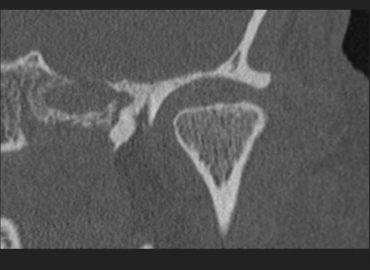

15 años. Gonalgia. Trauma hace 6 meses